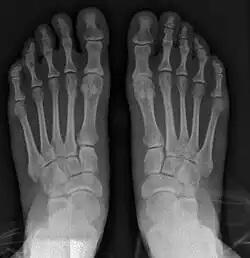

- For recurrence correction after osteotomy procedure (Fig. 8)

Late deformity recurrence can happen after osteotomy (bone-breaking) procedures because osteotomy surgeries do not specifically stabilize first metatarsal bone.